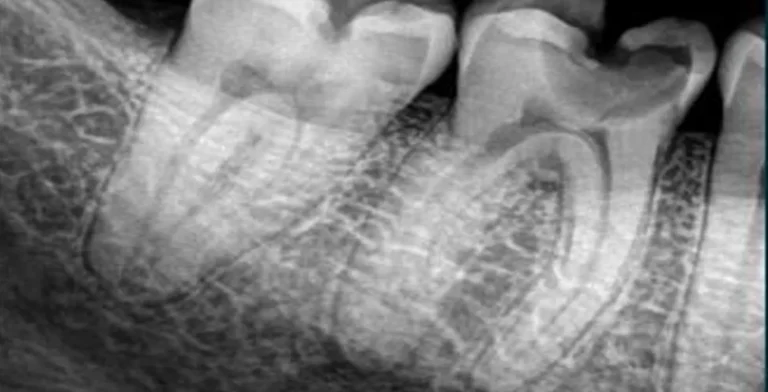

Root Canal Treatment

Root canal treatment in Türkiye

At Dream  Clinic, our expert dentists use state-of-the-art techniques to perform root canal treatments with precision and comfort, restoring your dental health and preserving your smile.